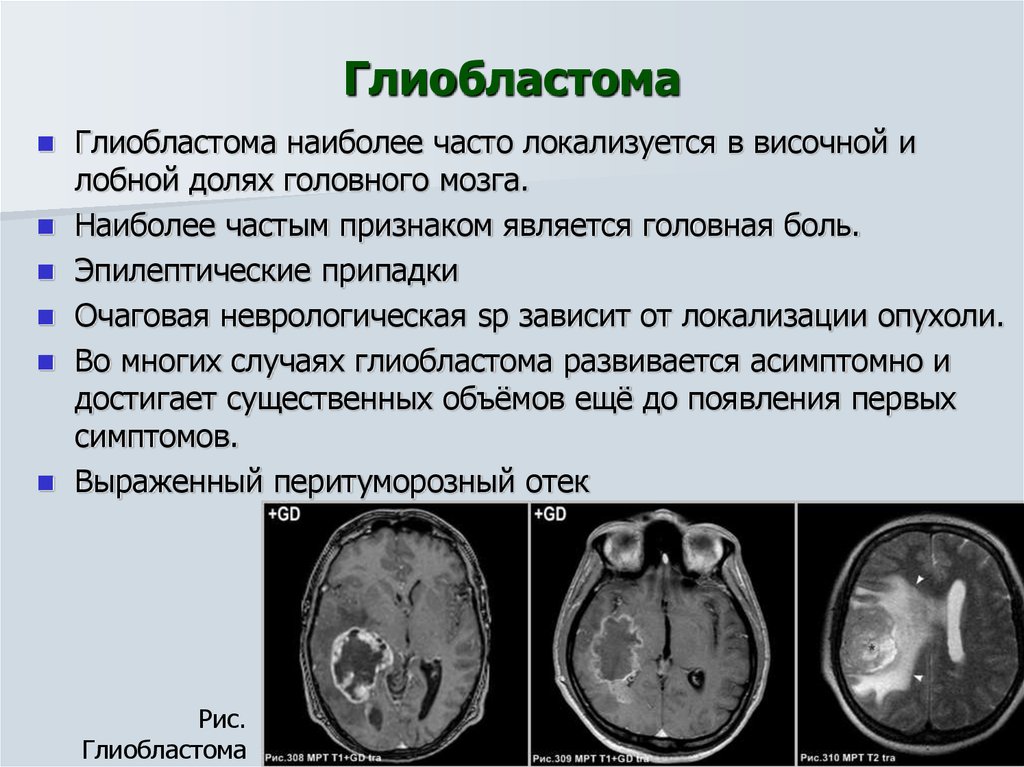

Лучевая диагностика опухолей поджелудочной железы. Методы диагностики патологии поджелудочной железы. Методы исследования поджелудочной железы. Метод исследования поджелудочной железы. Опухоль головного мозга стадии. Опухоль головного мозга симптомы. Проявление опухоли головного мозга. Степени опухолей головного мозга.

Опухоль головного мозга стадии. Опухоль головного мозга симптомы. Проявление опухоли головного мозга. Степени опухолей головного мозга. Методы исследования при опухоли головного мозга. Дополнительные методы исследования опухолей головного мозга. Диагноз кт с опухолью головного мозга. Дополнительные методы исследования при опухолях головного мозга.

Злокачественные заболевания молочных желез. Новообразование молочной железы. Злокачественная опухоль молочной железы. Доброкачественные новообразования молочной железы. Очаговые симптомы опухоли затылочной доли. Клинические проявления опухоли лобной доли:. Опухоль мозга височной доли симптомы. Опухоль затылочной доли головного мозга.

Очаговые симптомы опухоли затылочной доли. Клинические проявления опухоли лобной доли:. Опухоль мозга височной доли симптомы. Опухоль затылочной доли головного мозга. Гепатомегалия. Симптомы гепатомегалии. Умеренное увеличение печени. Умеренная гепатомегалия.

Фиброаденома молочной железы дифференциальный диагноз. Новообразование молочной железы фиброаденома. Диф диагноз фиброаденомы молочной железы. Фиброаденома молочной железы 30мм-37мм. Диагностические критерии глиомы головного мозга. Особенности опухолей лобной доли. Клиника опухоли затылочной доли головного мозга. Симптомы, характерные для опухолей лобной доли.

Диагностические критерии глиомы головного мозга. Особенности опухолей лобной доли. Клиника опухоли затылочной доли головного мозга. Симптомы, характерные для опухолей лобной доли. Компьютерная томография с болюсным контрастированием. Кт толстой кишки с контрастированием. Кт с болюсным контрастированием что это.

Компьютерная томография с болюсным контрастированием. Кт толстой кишки с контрастированием. Кт с болюсным контрастированием что это. Глиобластома мультиформная степень 4. Неоперабельная глиобластома головного мозга.. Глиобластома лобной доли мрт. Глиобластома злокачественная опухоль агрессивная.

Глиобластома мультиформная степень 4. Неоперабельная глиобластома головного мозга.. Глиобластома лобной доли мрт. Глиобластома злокачественная опухоль агрессивная. Филлоидная фиброаденома молочной железы УЗИ. УЗИ признаки доброкачественных опухолей молочных желез. Доброкачественная опухоль молочной железы на УЗИ. Опухоль молочной железы на УЗИ.